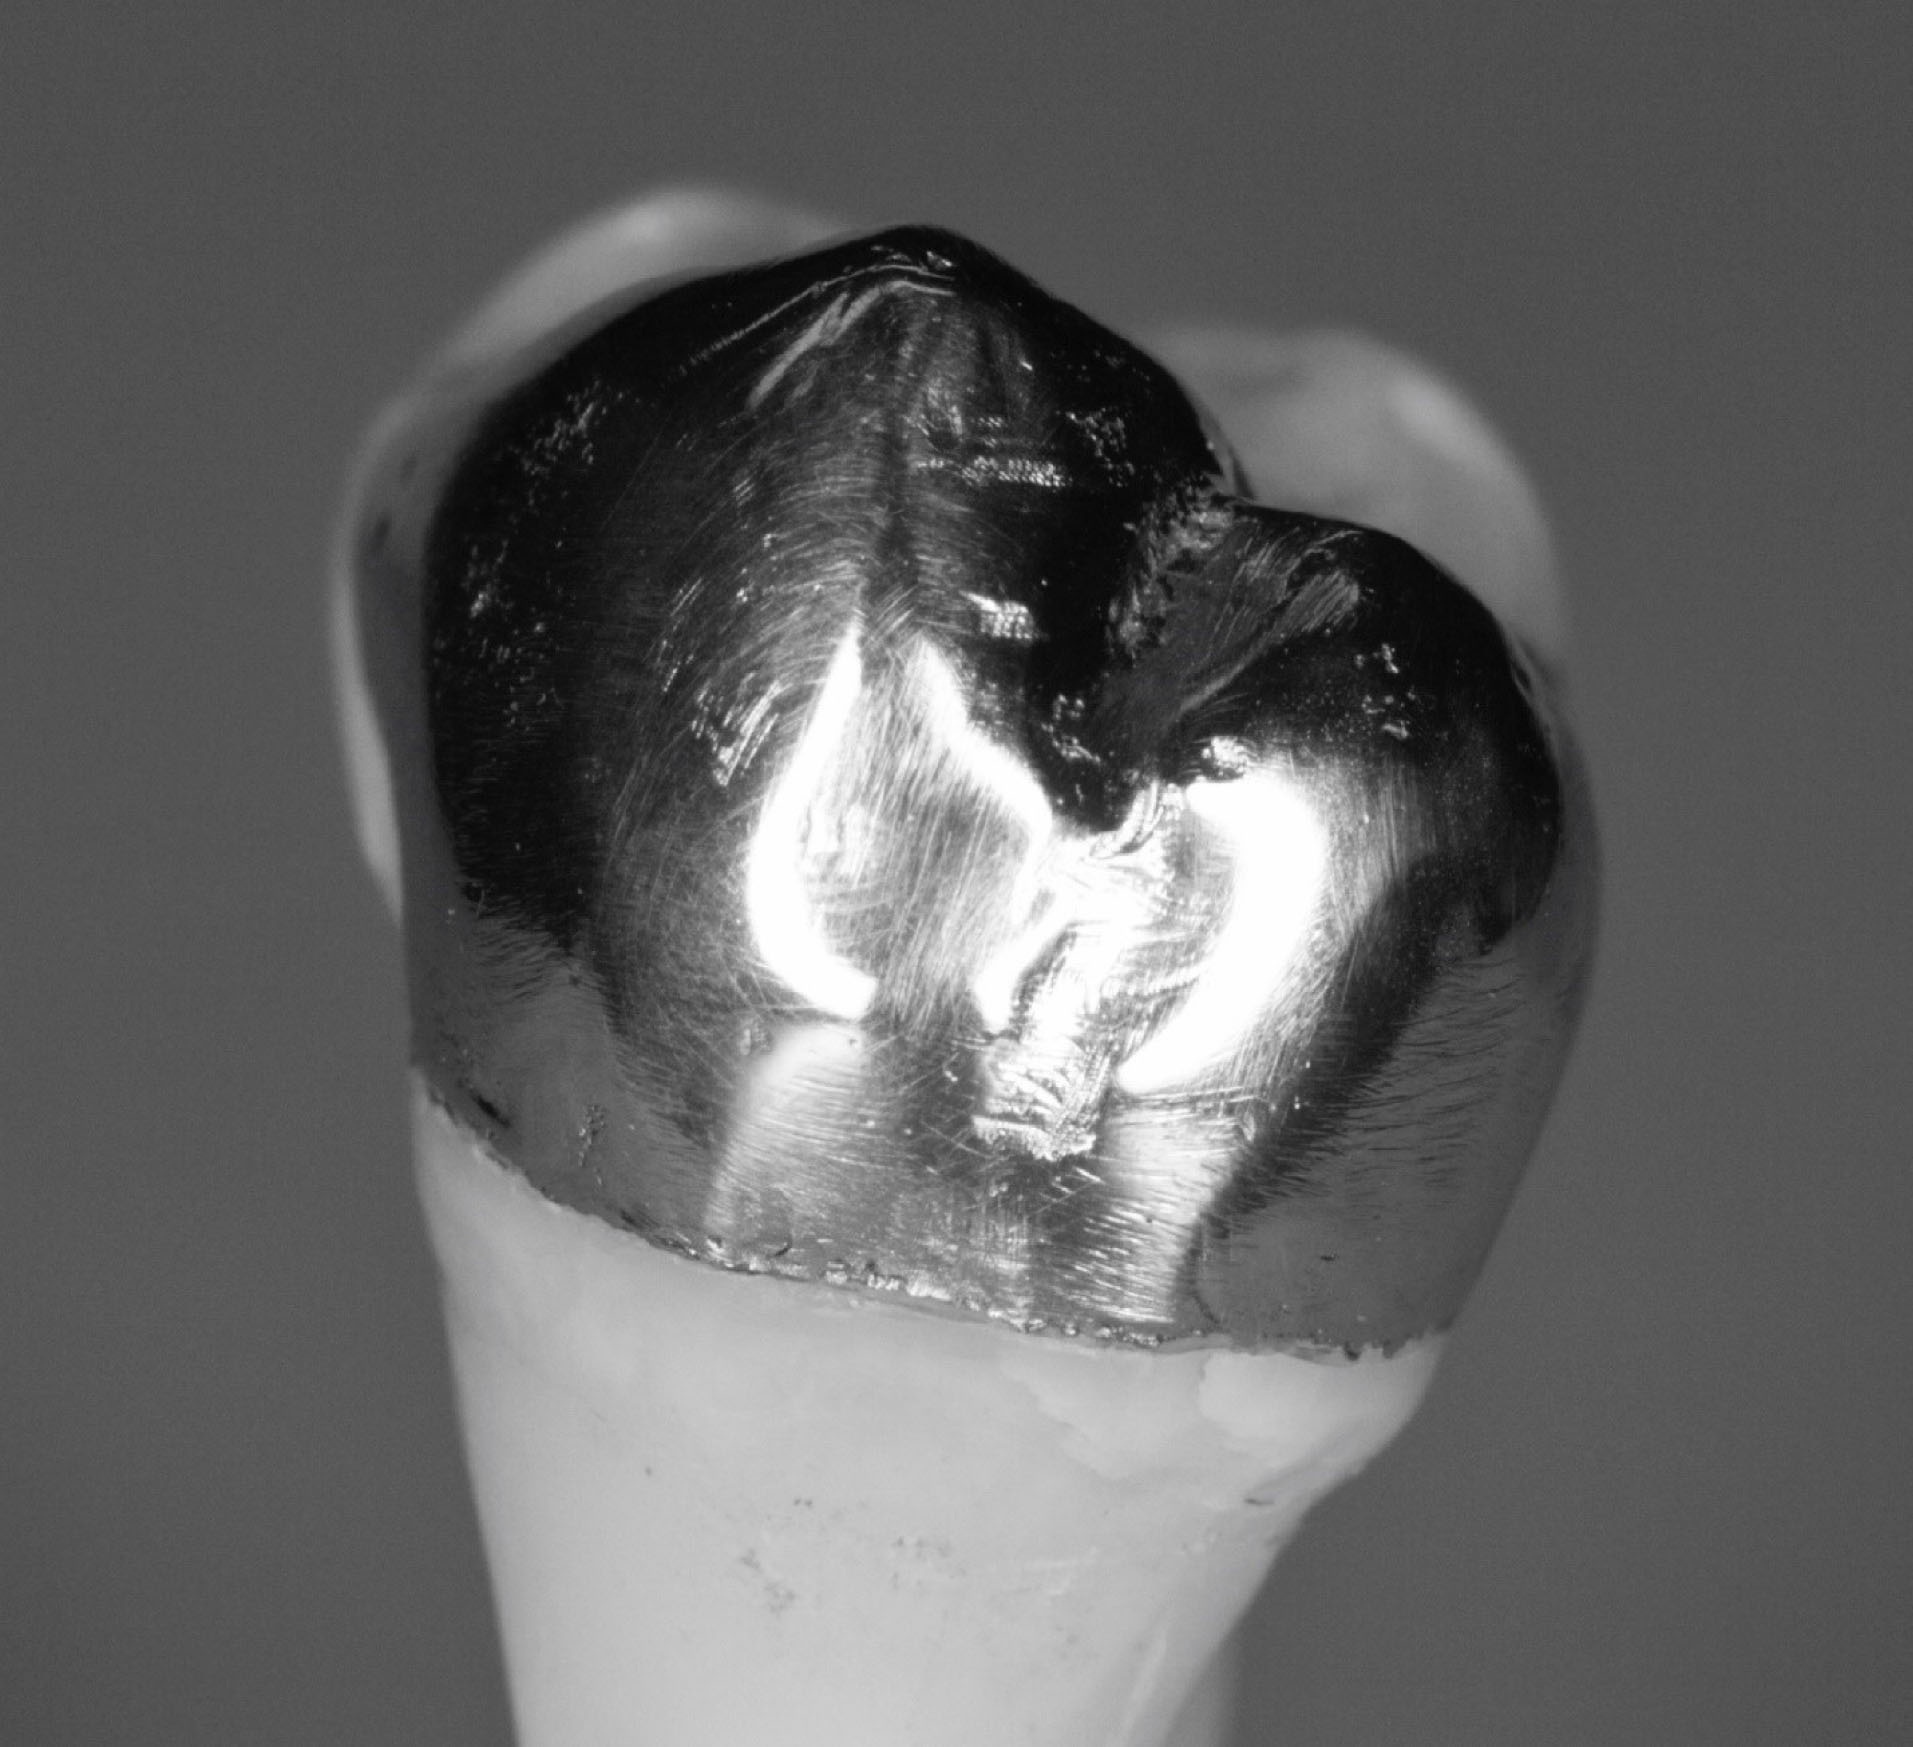

Figure 7. Photograph of the occlusal view of cemented onlay.

joddd-15-147-g008

Each onlay was bonded to its corresponding prepared tooth using resin cement (GC, Alsip, United States) following the manufacturer’s protocol. 5 The restorations were then polished with high-speed diamond burs and slow-speed finishing discs. Post-cementation photographs were taken of the restorations in buccal, lingual, mesial, distal and occlusal views ( and ). Radiographs were also taken for each restoration in mesiodistal and buccolingual aspects ( and ).

The digital scanner provided an STL file of suitable resolution for three-dimensional (3D) printing in metal. The indirect onlay restorations were successfully 3D-printed in cobalt-chromium with dimensions, morphology, and fit clinically acceptable for subsequent cementation. Cementation was unremarkable and adequately retained the onlays, similar to previous investigations. 6 Marginal adaption was generally acceptable but was clinically unacceptable in one area due to an open margin. The surface finish was generally acceptable but could be improved in some areas, especially on the occlusal surface.

This preliminary study demonstrated that the workflow of additive manufacturing of cobalt-chromium onlays, without digital design, is possible. For predictability, the scanner and printer must have an adequate resolution. The printed final restoration quality depends on the provisional; therefore, a highly morphologically accurate, ideally adapted (margins), and polished provisional is mandatory, as cobalt-chromium is difficult to polish. The preparation was suitable for the material.